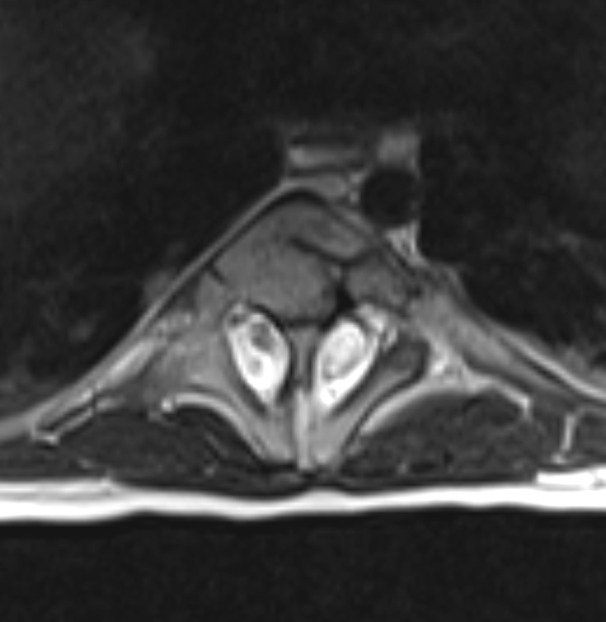

The skin of all the subjects had signs at the region of the back, similar to local hypertrichosis, hemangiomas, or skin dimpling (a representative image is shown in Fig. 2). Widening of the interpedicular distance at the level of one or a few vertebral segments is a very distinctive feature for patients with diastematomyelia as shown in Fig. 3. In such cases, the presence of spinal cord splitting was clearly visualized on MRI (Fig. 4). CT images provided the necessary information to differentiate between bony and fibrotic septum (Fig. 5). In our population, 18 (90%) subjects had different types of congenital vertebral anomalies, including failure of formation, segmentation and a combination of aforementioned, while 17 (85%) subjects had congenital scoliosis. In 2 (10%) subjects with fibrotic septum, there were no congenital abnormalities. The most commonly seen musculoskeletal deformity in subjects with diastematomyelia was lower limb asymmetry. Atrophy with increasing muscle weakness was thought to be a case of neurological deterioration, thus being an indication for surgery. Partial restorations of neurological function were observed in total four subjects, for whom spur resection surgery was carried out.

Fig. 4.

MRI of the subject which shows cord split by the bony septum. Each has its own dural sac, which need to be sutured after spur resection and duraplasty